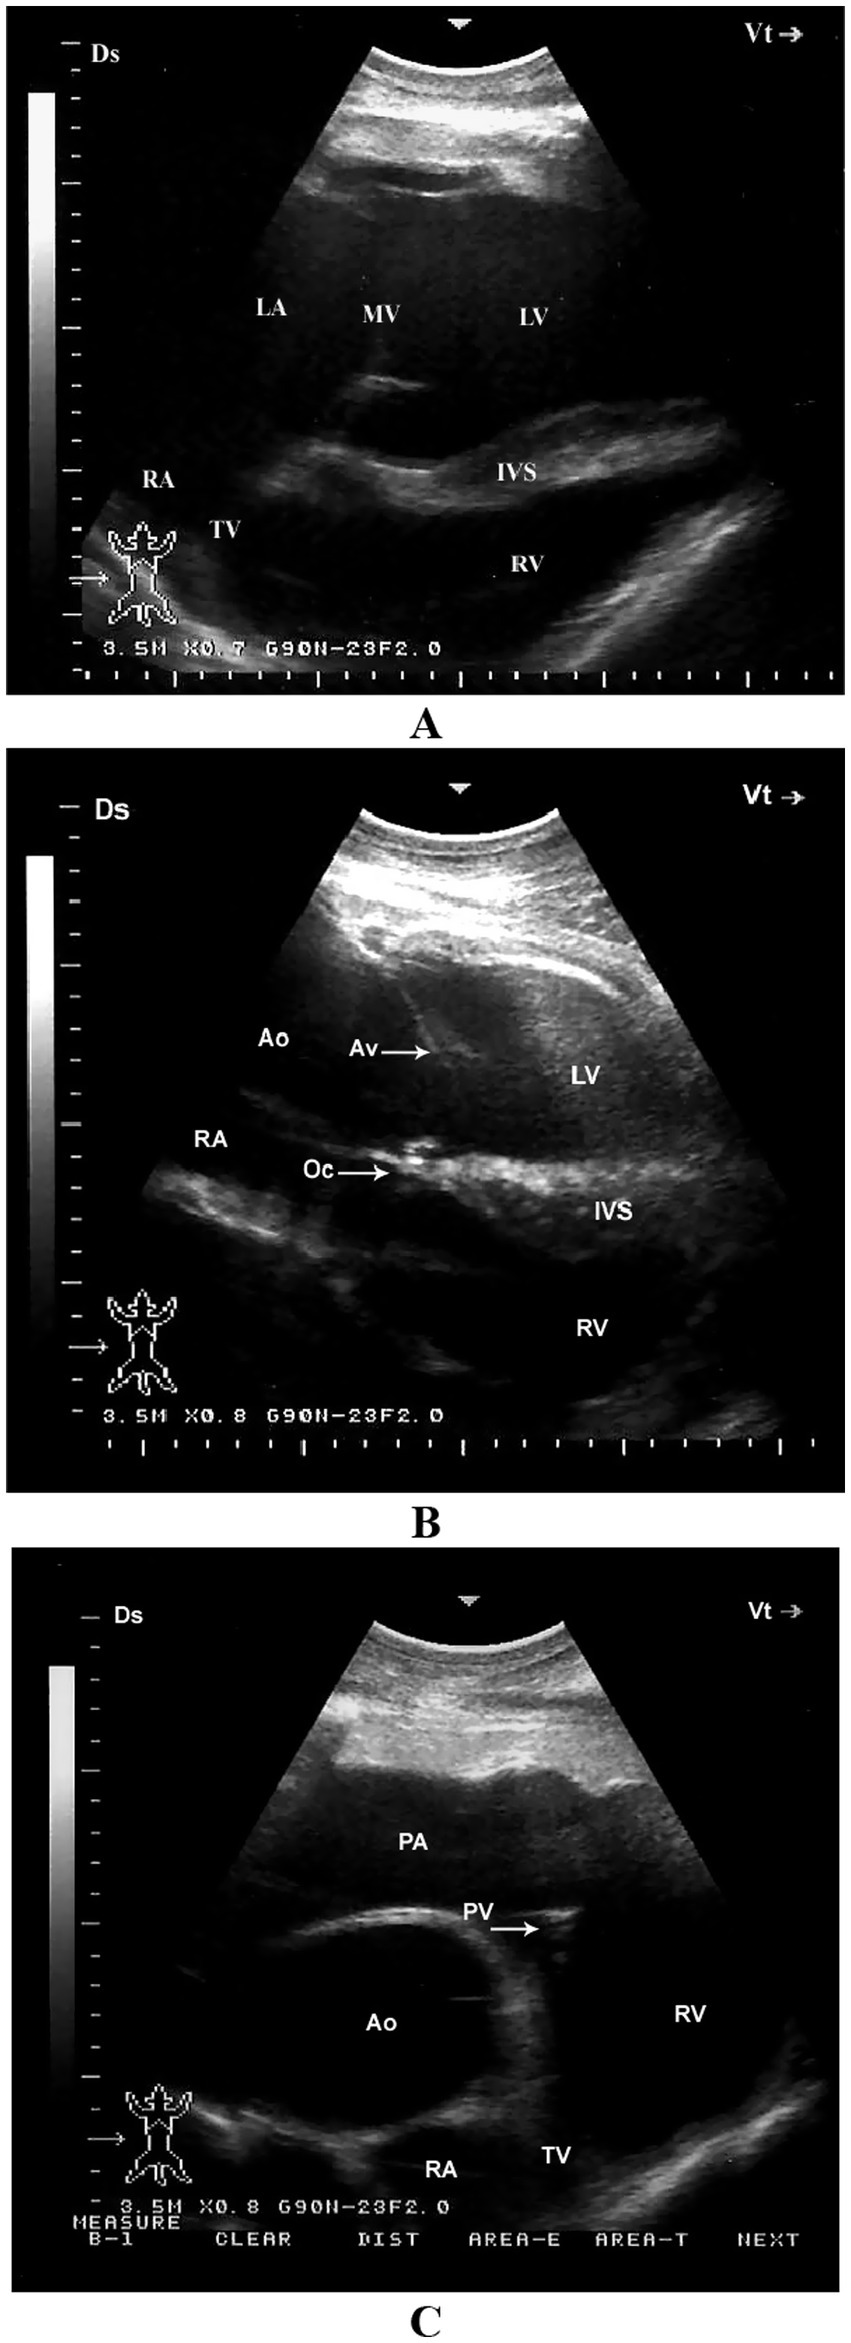

When the probe is placed longitudinally in the 4th or 5th intercostal space (ICS) and angled slightly caudodorsally, it allows visualization of the ventricles, atria, and atrioventricular valves. The LVOT can be imaged from the 4th ICS by directing the probe slightly more cranially and rotating it slightly counterclockwise. The RVOT is best visualized from the 3rd ICS. In this position, the right ventricle, tricuspid valve, right atrium, an oblique section of the aorta, and the pulmonary artery can be clearly seen (11) (Figure 5).

Figure 5. Left parasternal echocardiographic views in a healthy dromedary camel. (A) Caudal long-axis view displaying all four cardiac chambers and atrioventricular valves, enabling comprehensive assessment of chamber dimensions and valve function. (B) Left ventricular outflow tract view with the aortic valve seen as a thin echoic line in cross-section; this view assists in evaluating aortic valve morphology and detecting stenosis or regurgitation. (C) Cranial long-axis view highlighting the right ventricular outflow tract and aortic root, useful in identifying structural abnormalities in the outflow tract and assessing great vessel alignment. Ds, dorsal; Vt, ventral; RV, right ventricle; RA, right atrium; TV, tricuspid valve; Ao, aorta; PA, pulmonary artery; PV, pulmonary valve; LV, left ventricle; IVS, interventricular septum; AV, aortic valve; Oc, ossa cordis; LA, left atrium; MV, mitral valve [adapted from Tharwat et al. (11)].